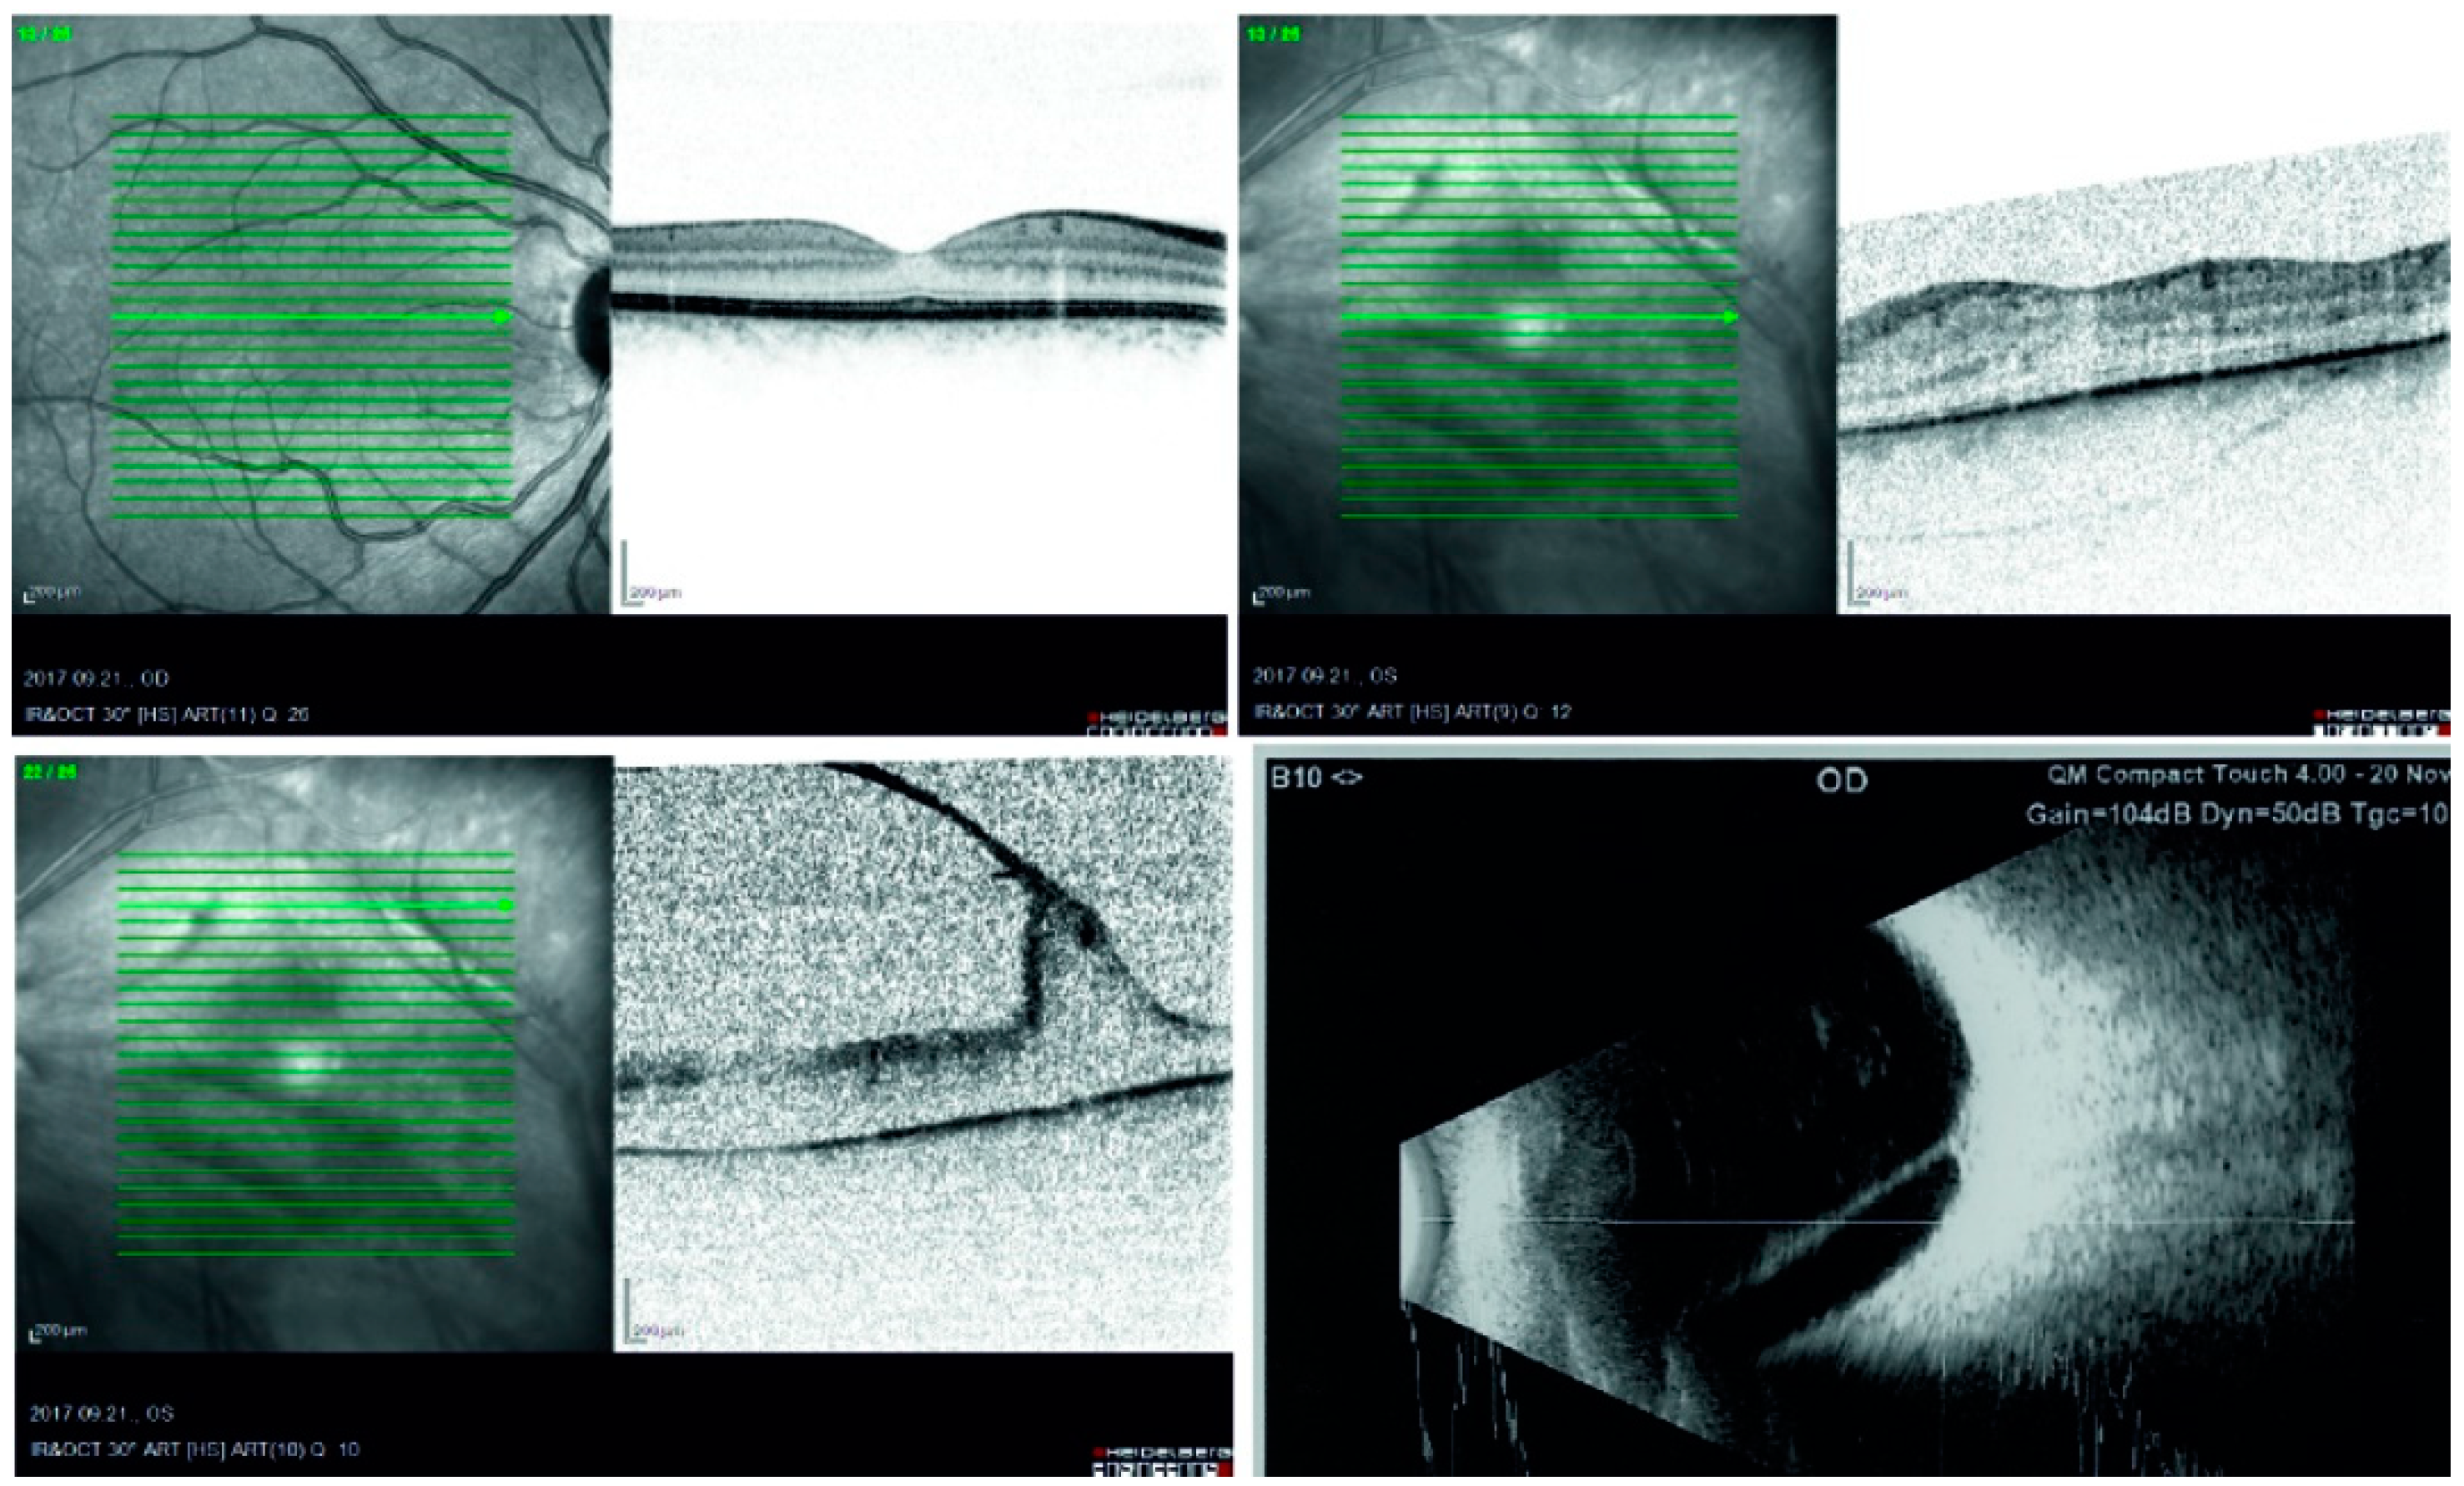

Immunohistochemical Analysis of a Vitreous Membrane Removed from a Patient with Incontinentia Pigmenti-Related Retinal Detachment

2. Case Report